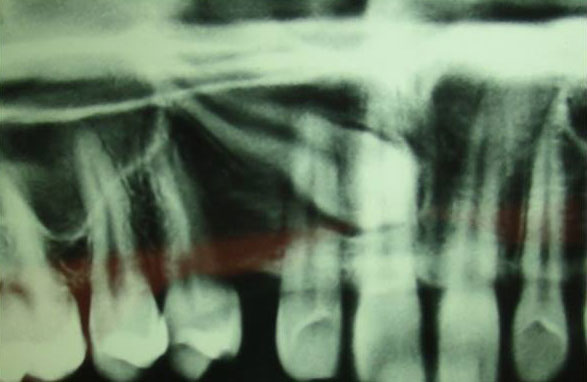

Canines being the last upper teeth to erupt lose their way sometimes… |

They can cause facial asymmetry and an unbalanced smile… |

The missing Canine |